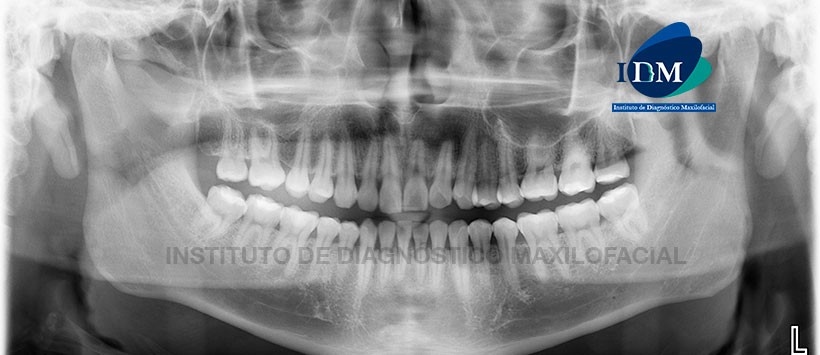

Paciente masculino de 28 años de edad, es referido al Instituto de Diagnóstico Maxilofacial (IDM) para evaluación general.